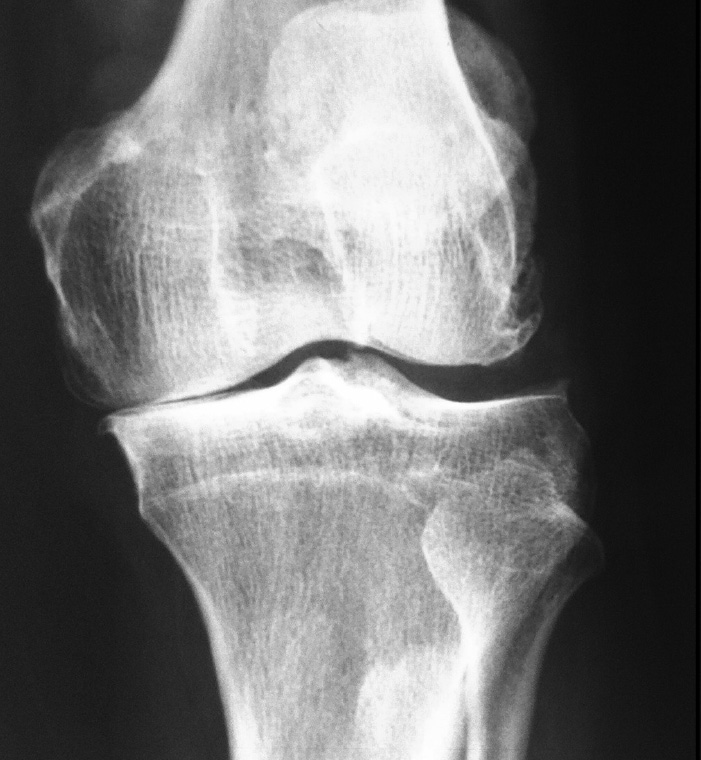

Sin embargo, el desgaste por lesiones del cartílago traumáticas, por envejecimiento (osteoartritis), por secuelas de fracturas o traumatismos, una mala alineación de la articulación o no resueltas en tiempo y forma, alteran dicha armonía en la función articular provocando de manera progresiva dolor, rigidez articular, debilidad muscular y disminución de la función.

La principal causa del dolor crónico de la rodilla que condiciona discapacidad por desgaste articular es la osteoartrosis, sin embargo, la artritis reumatoide y el desgaste articular postraumático, son causas frecuentes de lesión del cartílago de manera extensa y acelerada.

• La osteoartrosis es un tipo de enfermedad articular por uso, envejecimiento y desgaste relacionado con la edad. Habitualmente se presenta en personas mayores de 50 años.

• El desgaste articular pos-traumático se presenta después de una lesión seria de la rodilla, en específico, fracturas del hueso y cartílago que conforman la articulación y lesiones de los ligamentos que estabilizan la articulación no resueltas o crónicas.